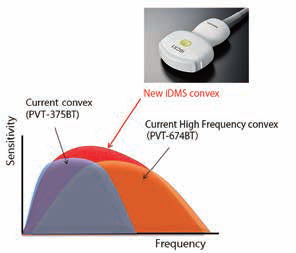

Система Aplio i-серії оснащена ультраширокосмуговим конвексним датчиком з iDMS PVT-475BX. Ультраширокосмуговий датчик призначений для покриття частотного діапазону, який зазвичай покривається двома датчиками, щоб забезпечити як високу роздільну здатність, так і глибину проникнення.

Малюнок 3. Ультраширокосмугові опуклі датчики iDMS